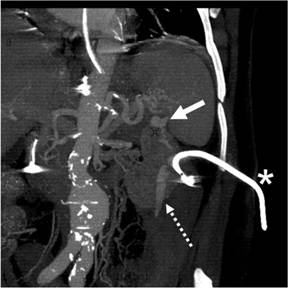

Shortly after the procedure, the patient developed three episodes of massive haematochezia overnight. An urgent CT scan demonstrated a splenic artery pseudoaneurysm and haemorrhage from the splenic artery into the splenic flexure of the colon and blood in the descending colon (Figures 1 and 2).

Figure 1. Coronal reformatted CT image demonstrates a splenic artery pseudoaneurysm (arrow), percutaneous drain (asterisk) and active extravasation of intravenous contrast (interrupted arrow) extending inferiorly from the region of the pseudoaneurysm and percutaneous drain. |